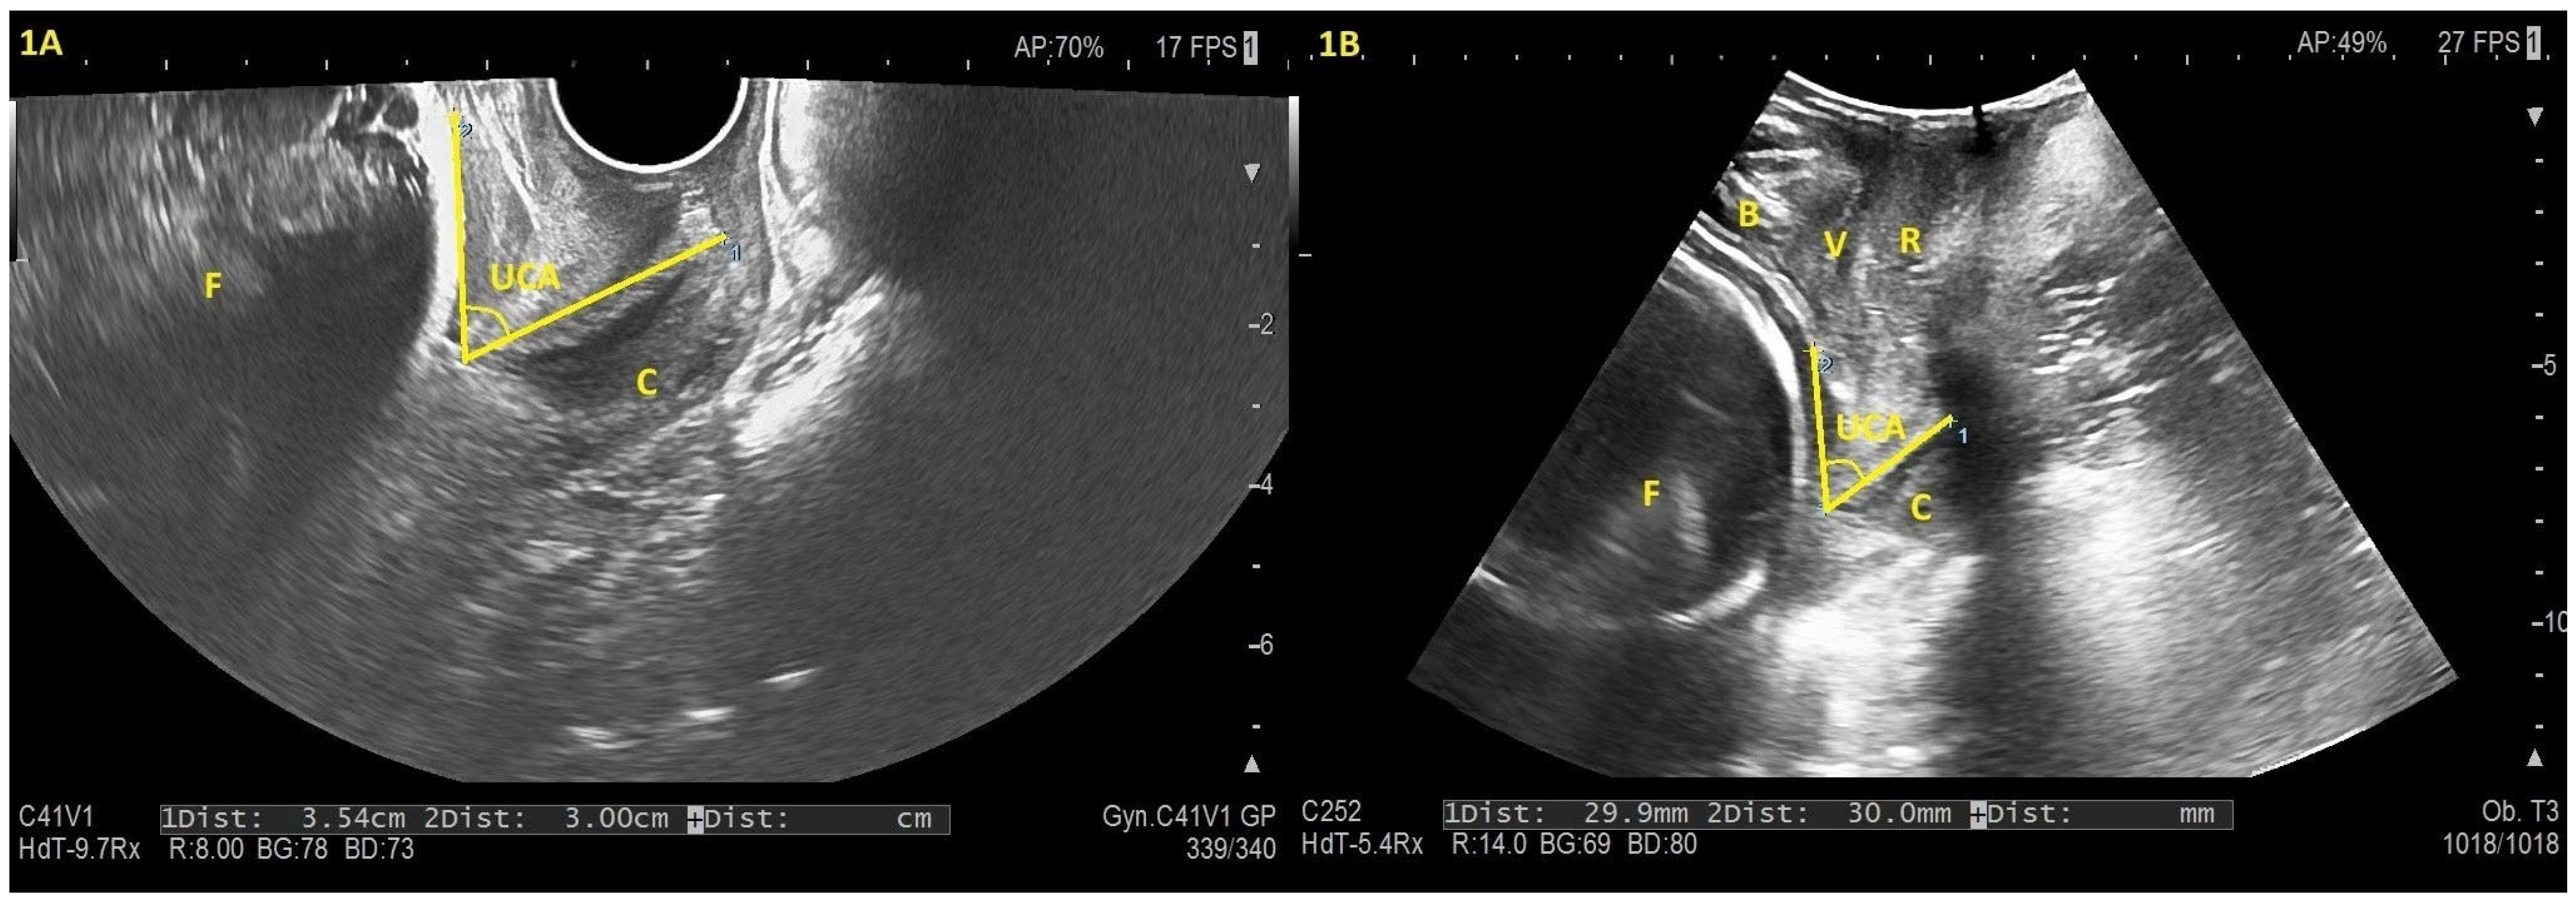

2.3. Data Sources/Measurement